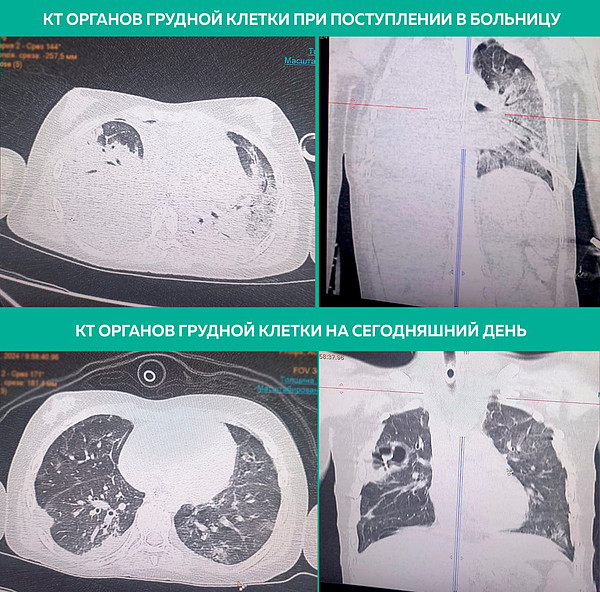

Врачи Кировской областной детской больницы спасли девочку с 95-процентным поражением легких